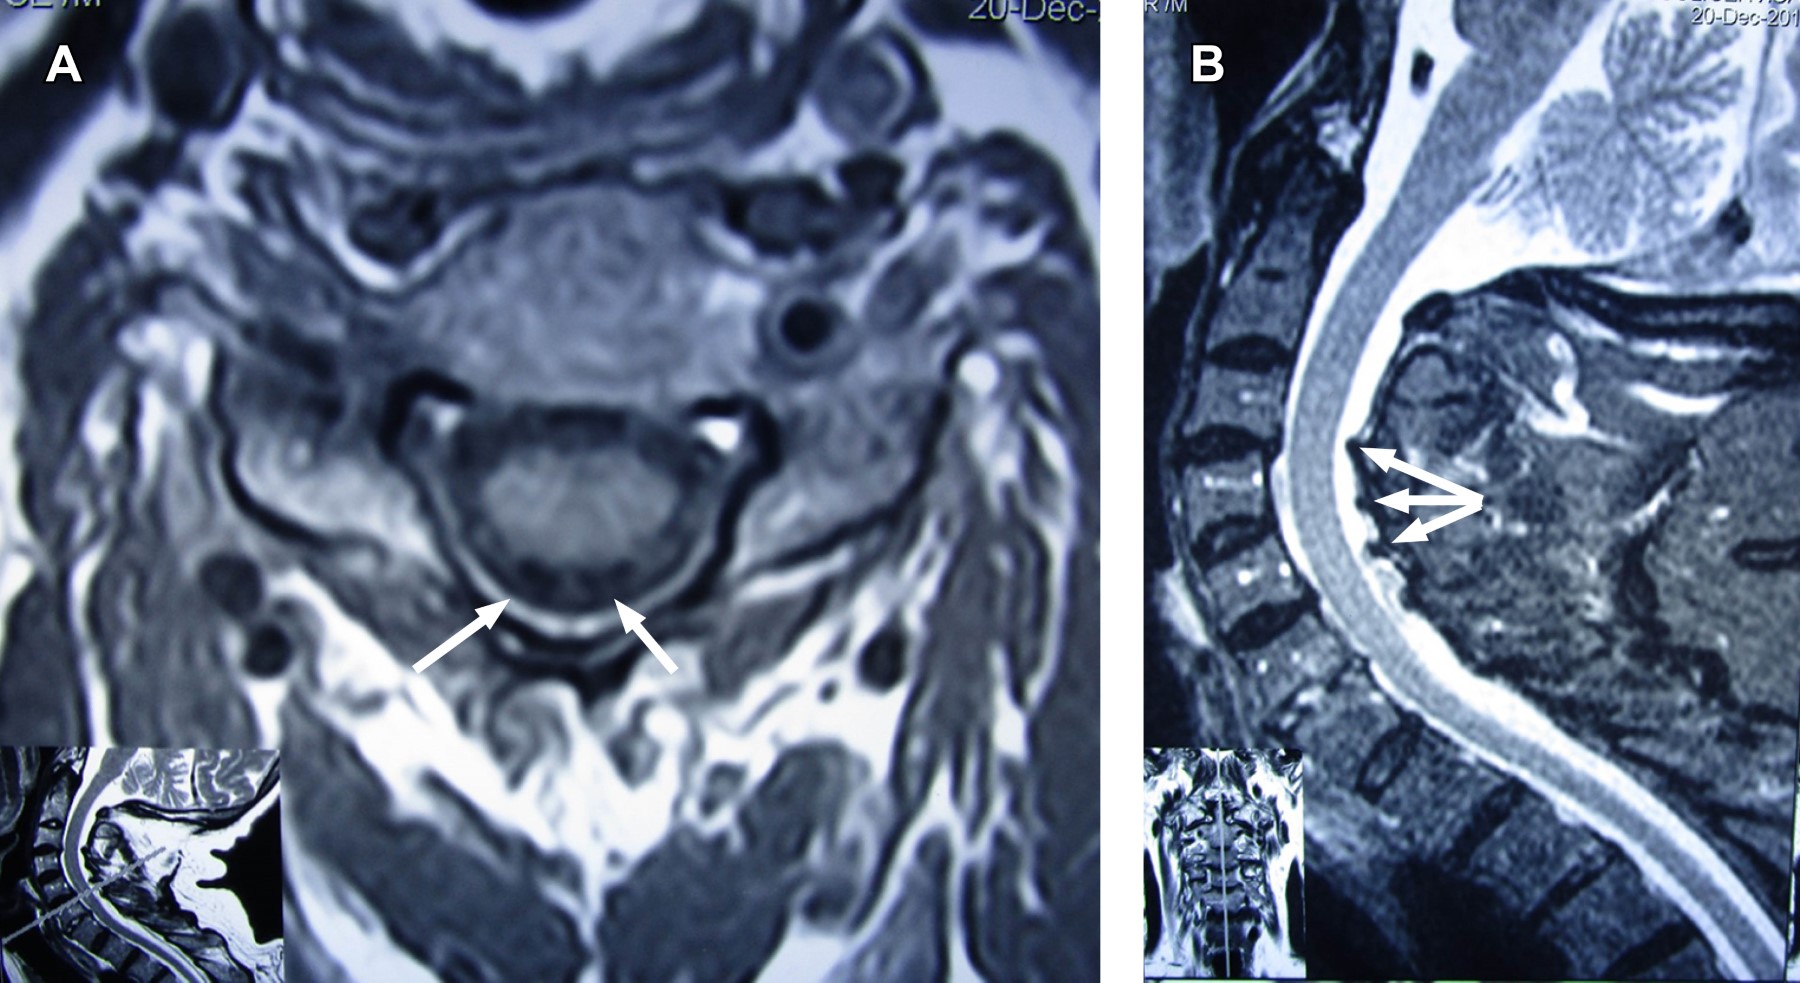

Con los datos clínicos se establece diagnóstico de síndrome de lesión del cordón medular posterior, específicamente del fascículo gracilis, sustentado en pérdida de la sensibilidad propioceptiva, epicrítica y vibratoria por debajo de C7 y marcha atáxica con signo de Romberg positivo y miembros superiores normales, pues se consideró que el plegamiento del ligamento amarillo y de la duramadre pudieran contribuir a la compresión dorsal de la médula espinal en la hiperextensión, causando presión sobre la médula espinal. Por lo que se efectuó resonancia magnética cinética de columna cervical (Figuras 1 y 2), la cual confirmó el diagnóstico, por lo que se le programó para cirugía de columna cervical.

Figura 1